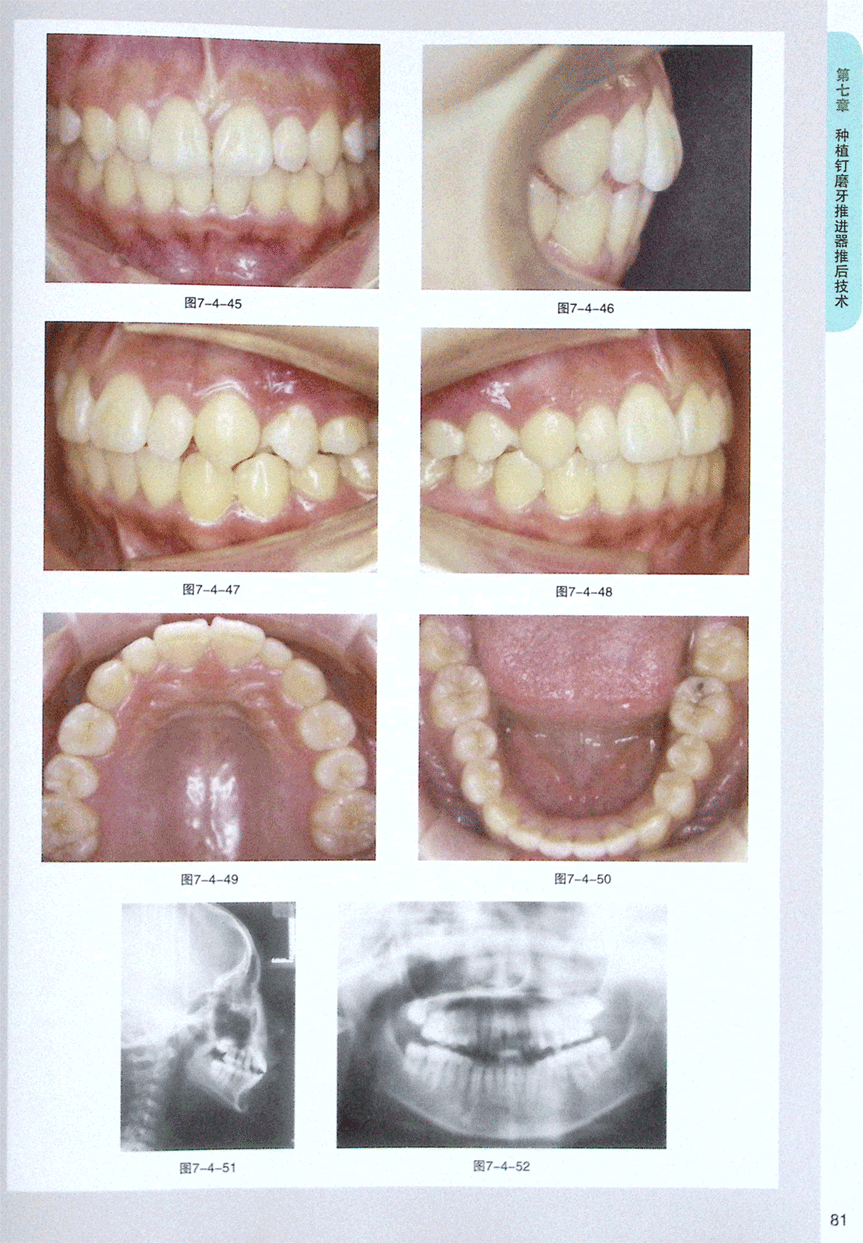

第四节 种植钉磨牙推进器推后矫治案例(2)